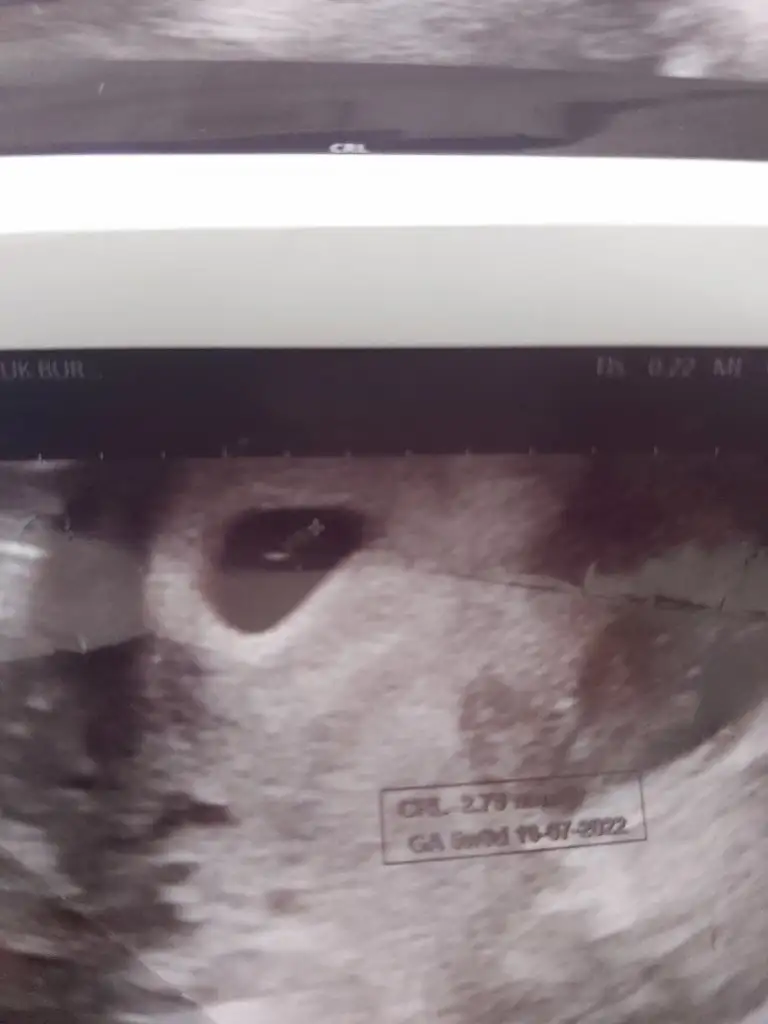

Canim benim 7. Haftamda var ilk ultrasonum yolluyorum sana5+6 yani 6.haftamdaki usg’de belli oldu teori, senin de varsa 6-7.haftaya kadar bakalım beraber tutacak mı

Canim benim 7. Haftamda var ilk ultrasonum yolluyorum sana

Bu arada bu karın ultrasonum5+6 yani 6.haftamdaki usg’de belli oldu teori, senin de varsa 6-7.haftaya kadar bakalım beraber tutacak mı

Sanki sola daha yakın gibi canım, erkek gibi yani ne dersinCanim benim 7. Haftamda var ilk ultrasonum yolluyorum sana

Canim kesenin içinde nereye yakin oldugu onemli degil mi bu teoride ? Burada solda duruyor bence deSanki sola daha yakın gibi canım, erkek gibi yani ne dersin

Evet canım, kesede sola daha yakın geldi bana da, ve karındansa erkek demekmiş ya..Canim kesenin içinde nereye yakin oldugu onemli degil mi bu teoride ? Burada solda duruyor bence de